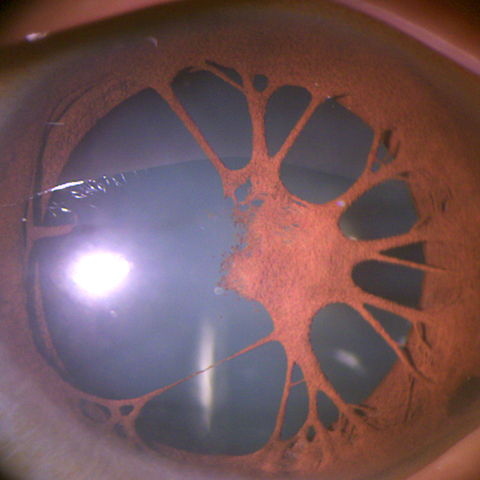

Spontaneously dislocated lens with ring-shaped pigmentation